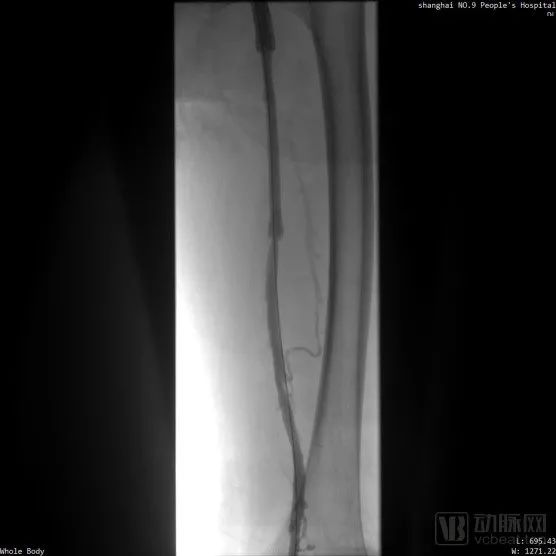

取栓术前管腔造影